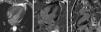

Case reportA 56-year-old Caucasian patient with COPD (irregularly treated with tiotropium bromide, acetylcysteine and mometasone) was admitted to the emergency room (ER) of our hospital with dyspnea and cough with sputum for two weeks. On admission to the ER, the patient was hemodynamically stable (systolic/diastolic blood pressure: 126/65 mmHg; heart rate: 98 bpm), eupneic at rest and with fever (39.1°C). Pulmonary auscultation revealed rumbles in the left hemithorax. The chest radiograph showed left paratracheal consolidation. There was no evidence of respiratory failure on arterial blood gas analysis. Laboratory tests revealed elevated leukocytes. After treatment with inhaled ipratropium bromide, the patient suffered severe bronchospasm and retrosternal chest pain accompanied by sweating and pallor. An electrocardiogram (Figure 1A), with pain, showed sinus tachycardia (heart rate 110 bpm), incomplete right bundle branch block, 2-mm ST-segment elevation in leads V1–V3 and Q waves in leads V3–V6. Given the possibility of an acute coronary syndrome, emergency coronary angiography was carried out, which showed normal coronary arteries (Figure 2A and B), severe systolic dysfunction with mid-apical akinesia and basal hypercontraction (Figure 2C). The echocardiogram confirmed severe compromise of left ventricular systolic function (LVSF), with akinesia of the mid-apical segments and an aneurysm-like dilatation (Figure 3). During hospitalization the patient remained hemodynamically and electrically stable, but the electrocardiographic pattern evolved with T-wave inversion in the left anterior precordial leads (Figure 1B) and plasma troponin I was elevated (peak value 2.28 ng/ml). After further use of ipratropium bromide, on the second day of hospitalization, the patient developed a new episode of marked bronchospasm and respiratory acidosis (pH 7.29; pCO2 53 mmol/l). He was started on non-invasive ventilation and was treated with hydrocortisone, inhaled salbutamol and furosemide, with progressive clinical improvement. He was also started on antibiotics (azithromycin plus ceftriaxone), but microbiological screening (bacteriological study of sputum and search for urinary antigens of Streptococcus pneumoniae and Legionella pneumophila) was negative. There was no significant increase in C-reactive protein levels. Repeat chest radiograph documented pulmonary overinflation. To assess the severity of lung disease, respiratory function tests were performed, which revealed a severe obstructive ventilatory syndrome with lung hyperinflation. The patient underwent a chest computed tomography scan on the fifth day after admission that showed scattered bronchiectasis and a ground-glass pattern in the area of the left lower lobe bronchus. The setting was interpreted as an infection in the process of resolution. Echocardiographic reassessment (Figure 3B) on the sixth day of hospitalization showed recovery of LVSF, with no segmental wall motion abnormalities, which was confirmed by cardiac magnetic resonance imaging (LVEF 57%) with no areas of delayed enhancement (Figure 4). The patient was discharged seven days after admission, treated with lisinopril 2.5 mg/day and inhaled salmeterol/fluticasone propionate. At six months of follow-up, no events had been registered.

Cardiac magnetic resonance imaging. Cine true fast imaging with steady-state free precession in 4-chamber at end-systole (A) shows normal contractility of the left ventricular apex with complete resolution of apical ballooning; 4-chamber (B) and 2-chamber (C) delayed post-contrast imaging shows no abnormal myocardial enhancement.